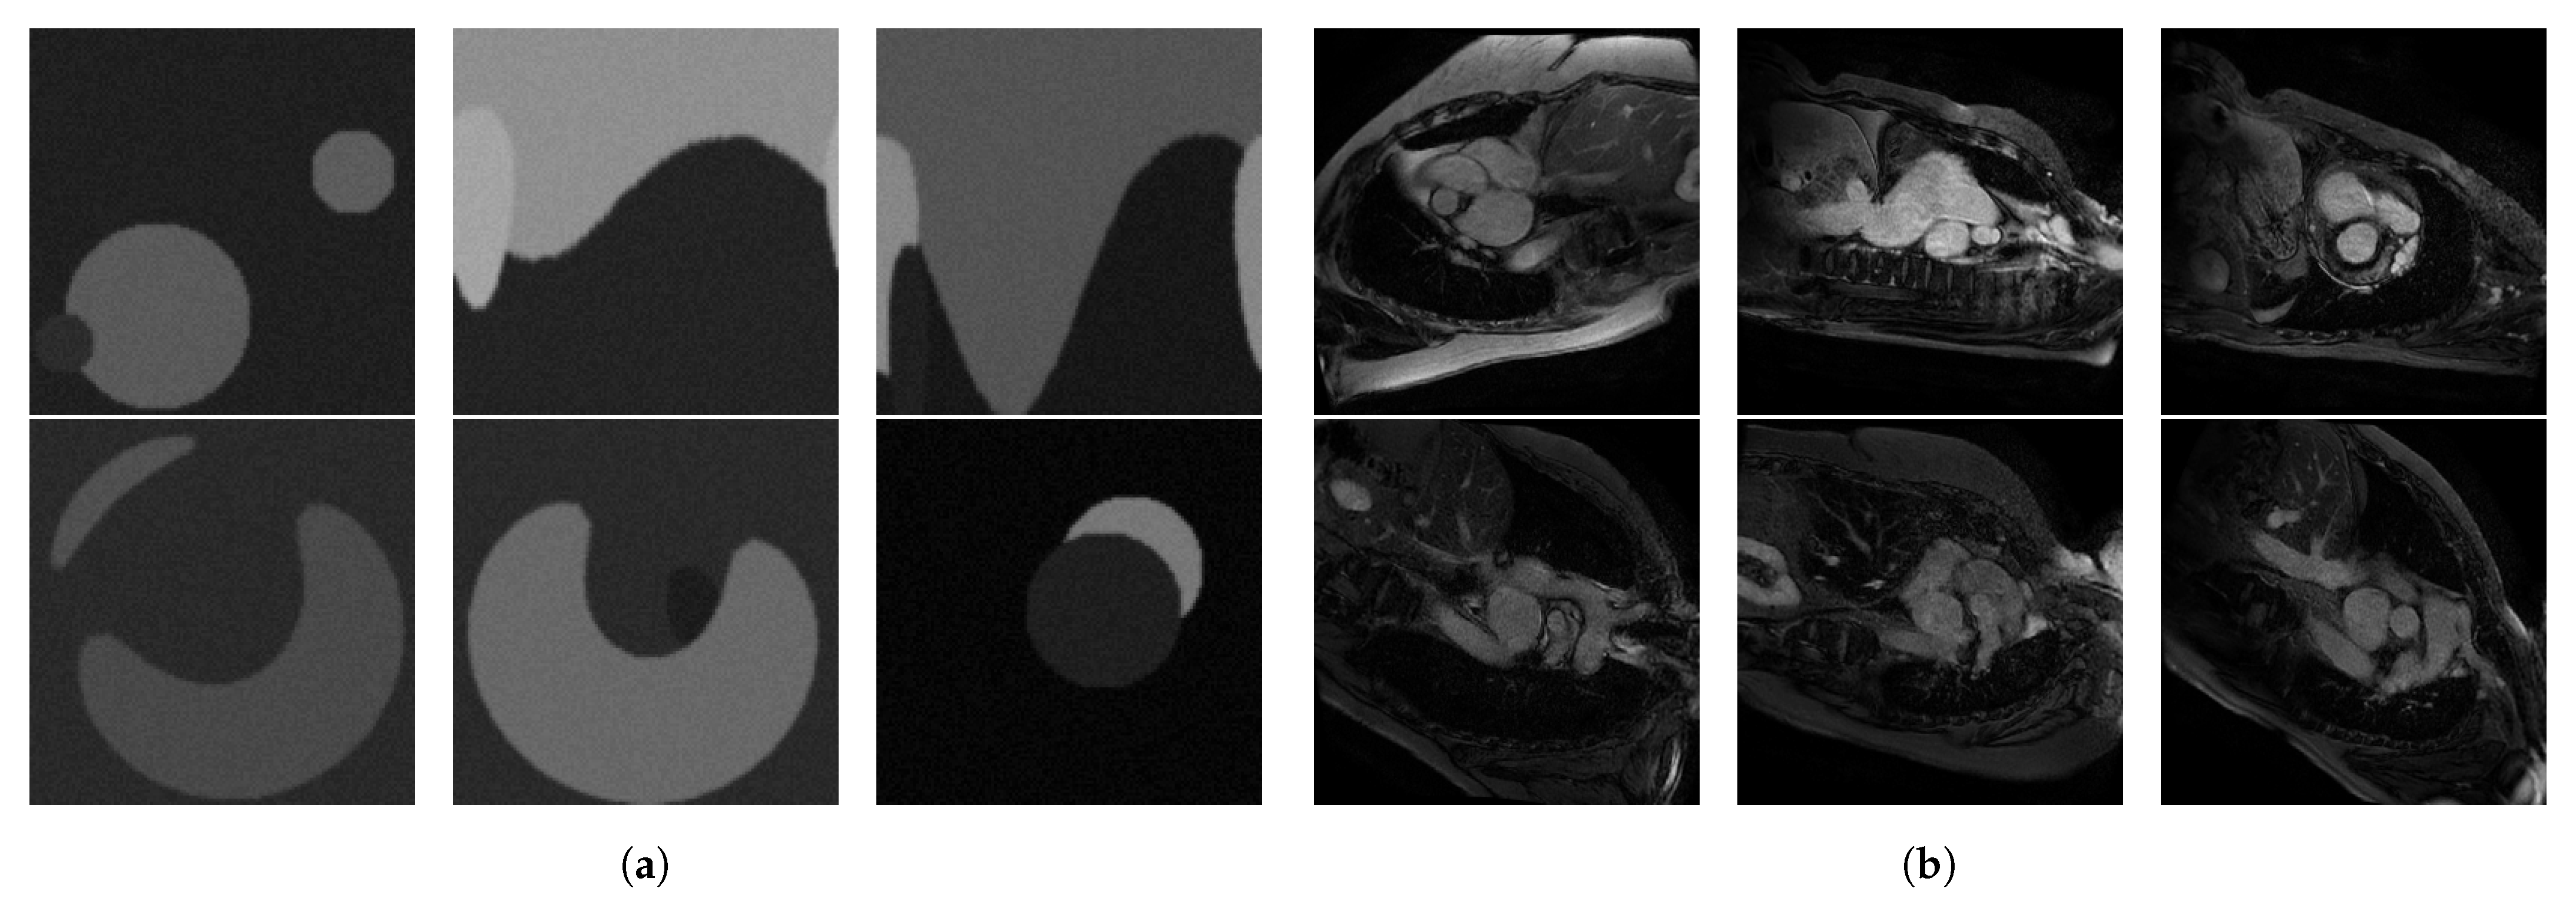

Upon visual assessment, we split the available MRI slices based on grey levels in two separate test sets, which we call low intensity and high intensity, respectively. To validate this split, we computed the average signal-to-noise ratio (SNR) over each resulted test set, and we obtained 2.570 ± 0.869 for the low intensity and 10.571 ± 3.66 for the high intensity set. The test sets contain 132 low intensity and 328 high intensity cardiac MRI slices from 32 patients and healthy volunteers from the imATFIB study. For the supervised rule optimization, we used synthetic training sets consisting of 20 low intensity and 20 high intensity images of circles of size 128 × 128 pixels. We used synthetic images because they are easy to produce, as opposed to MRI scans, and circular shapes emulate the types of structures found in our cardiac MRI. The images were filtered with a Gaussian filter and injected with Gaussian noise in order to better emulate MRI scans, and some of them were distorted. Examples from these datasets can be seen in Figure 2a,b for the high intensity set and Figure 3a,b for the low intensity set, respectively.

Figure 3. (a) High intensity optimization set, and (b) 6 representative images from the high intensity test set (imATFIB clinical study).